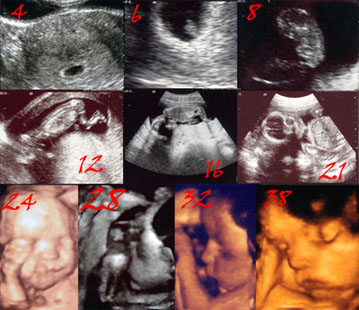

Bugüne kadar hamileyken hep aman nazar değer diye çoğunu yayınlamadım ultrasonlarımın. Ama doğumdan sonra bu mucizevi yolculuğu yayınlamayı çok istiyordum. İşte vakit o vakit. Özellike 4D ultrasonun nasıl acayip bir duygu olduğunu anlatmak zor. Karnımdaki bebeğin nasıl birine benzediğini 5. aydan itibaren biliyordum. Özellike son haftalarda yüzü dönük olan bebeği görmenin zor olmasından dolayı pek 4D bakılmıyor ama 38. haftada doktorumu bile şaşırtan bir poz verdi ki Erin.. hepimiz bir dakika bakakalmıştık. Doktorum bu haftada ilk defa bu kadar net bir görüntü aldığını söylemişti. Şimdi doğumdan sonraki ilk fotoğraflarına bakınca bu görüntülerin ne kadar net olduğunu göstermek için paylaşmak istedim burada.

32. haftada zaten belliymis hersey baksana , surat ayni gercekten inanilmaz!!!

Öykücüğüm ben hatta 24 ten beri belliymiş diye düşünüyorum 😉